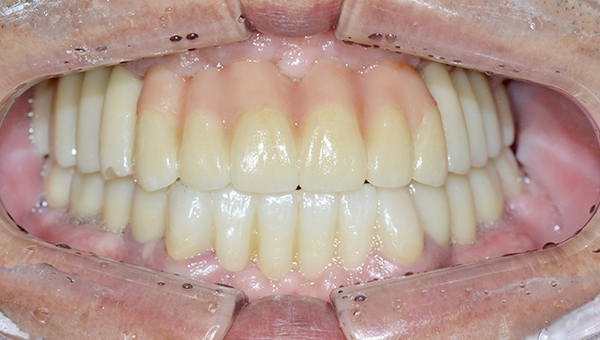

심*복 임플란트 시술 사례

전체 임플란트

2024.12.05

치료 전

2025.05.30

치료 후